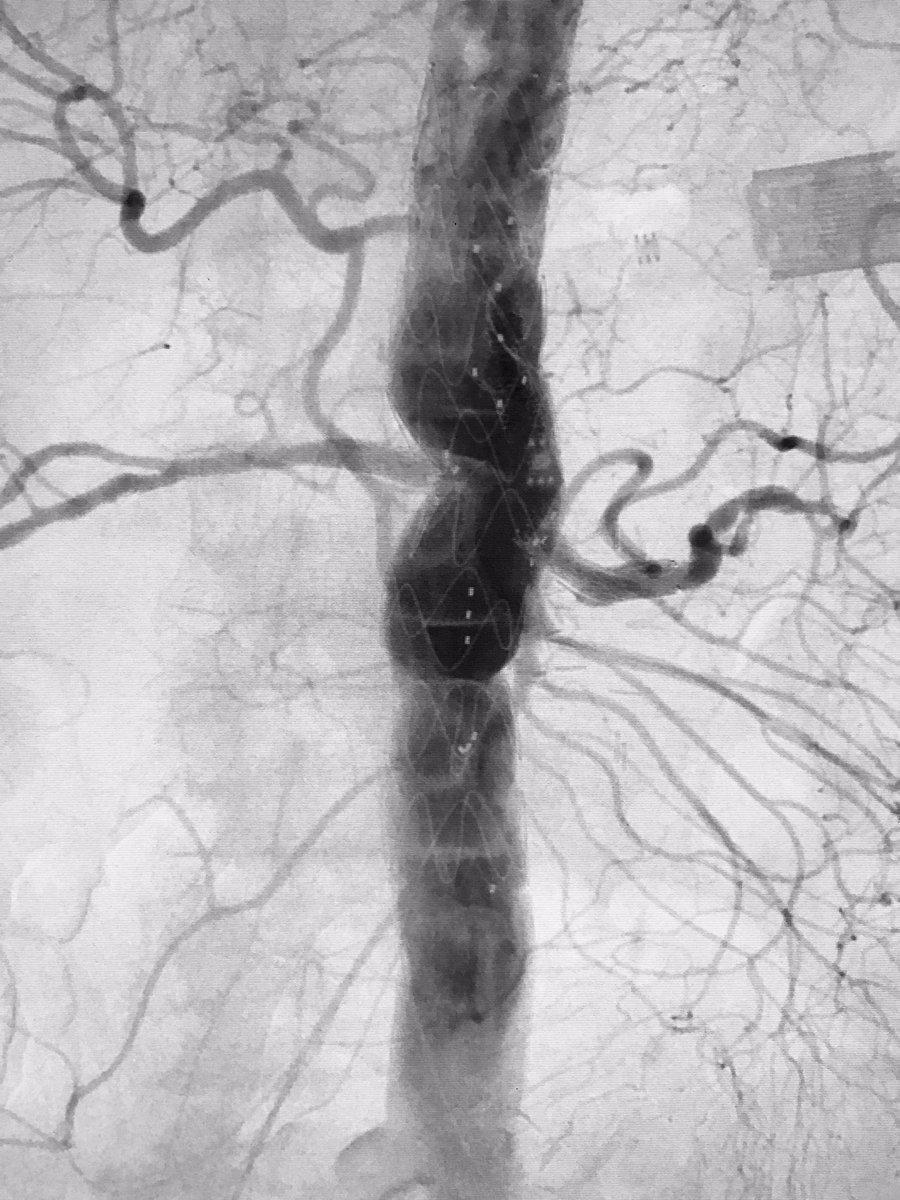

#DVT. IVC thrombosis. Single Session Endovascular Tx. #zelante Mount Sinai IR Jeff Mirviss Endovascular Today

4- vessel CMD FEVAR for treatment of type 4 thoracoabdominal aneurysm in our IDE study. That's how we roll! Weill Cornell Medicine NewYork-Presbyterian